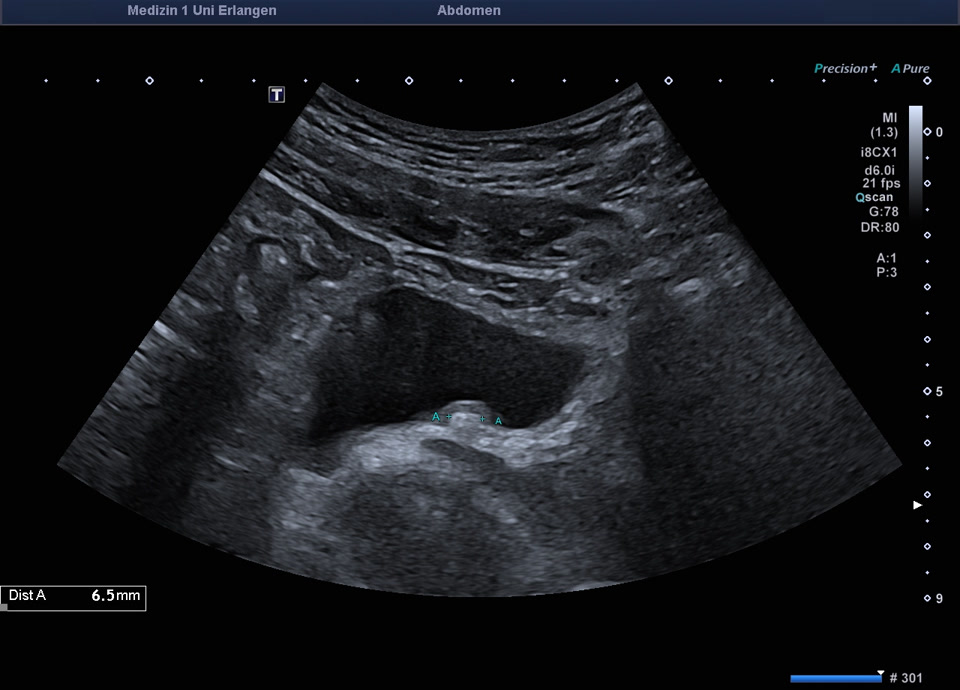

55-jähriger Patient mit abdominellen Beschwerden. Sonographisch stellt sich die linke Niere mit einem altersentsprechenden Parenchymsaum und regelrechter Mark-/Rindendifferenzierung dar. Das Nierenbeckenkelchsystem ist nicht erweitert. Distal im Bereich des Harnblasenostiums zeigt sich ein Konkrement von ca. 6 mm im Ureter, begleitet von positivem Twinkling-Artefakt im Farbdoppler. Der Ureter ist diskret erweitert, proximal bis 10mm. Sonographischer Befund vereinbar mit einer Ureterolithiasis im distalen linken Ureter (Ostium Harnblasenboden).